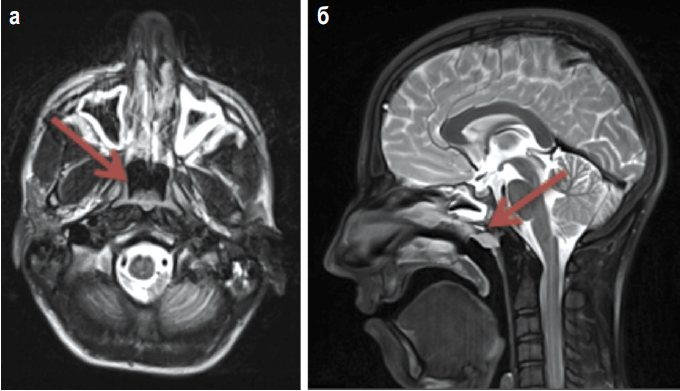

При очередном обследовании через 18 мес после завершения специального лечения по данным позитронной эмиссионной томографии, совмещенной с КТ, с 18F-дезоксиглюкозой возникли подозрения на рецидив РН. Основанием для этого был рост уровня накопления радиофармпрепарата в области небных и язычной миндалинах слева максимально до SUV 8,91 (ранее 5,11). Однако результаты магнитно-резонансной томографии носоглотки не показали признаков рецидива: в области свода носоглотки справа крайне неотчетливо сохранялись дополнительные ткани 1,0×0,9×0,5 см, не накапливающие контрастный препарат. Результаты представлены на рис. 3.

Рис. 3: а – стрелкой показан свод носоглотки с наличием нечетких дополнительных тканей; б – стрелкой показан свободный просвет носоглотки.

Fig. 3: a – the arrow shows the nasopharyngeal vault with the presence of indecipherable additional tissues; b – the arrow shows the clear lumen of the nasopharynx.